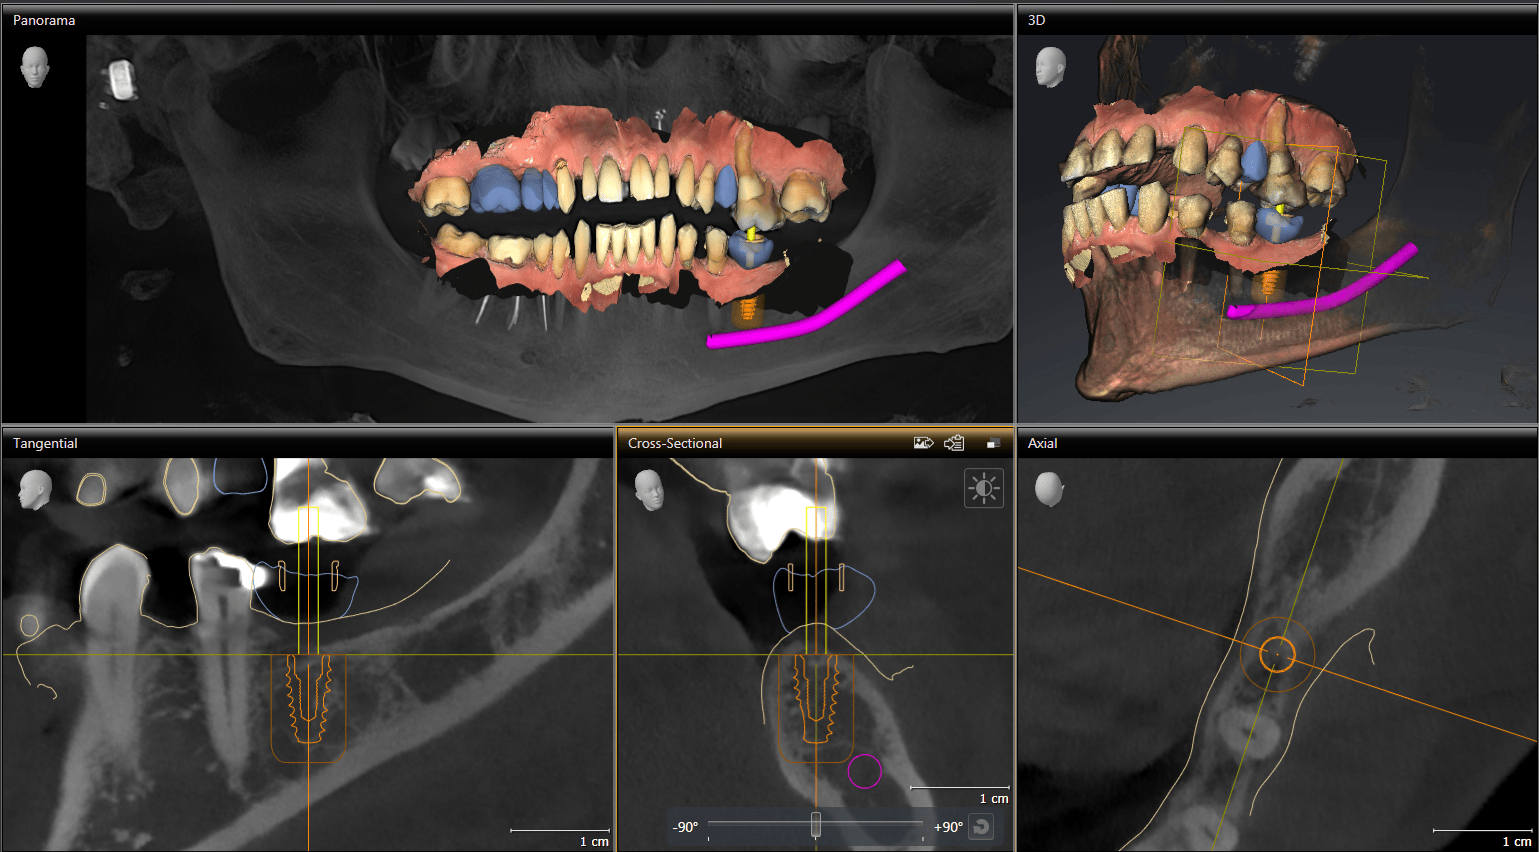

Guided implant surgery is a cutting-edge dental planning technique that combines advanced Sirona Axeos imaging and CEREC® computer technology to serve as a kind of map for precise dental implant placement. This method involves creating a 3D digital model of the patient’s mouth and design of an implant crown, which allows the dentist to visualize the anatomy and fabricate in-house, a customized surgical guide. This guide helps direct the exact placement, angle, and depth of each implant, ultimately making the process as safe and accurate as possible to produce results of the highest quality. This technique helps reduce the risk of complications, enhance recovery times, and lead to more predictable restorative outcomes. These factors often make it a preferred choice for both dentists and patients seeking reliable and efficient dental implant solutions.

In addition to Axios imaging, Sirona digital guides technologies allow for enhanced surgical precision through detailed 3D dental scans and computer-aided treatment planning.